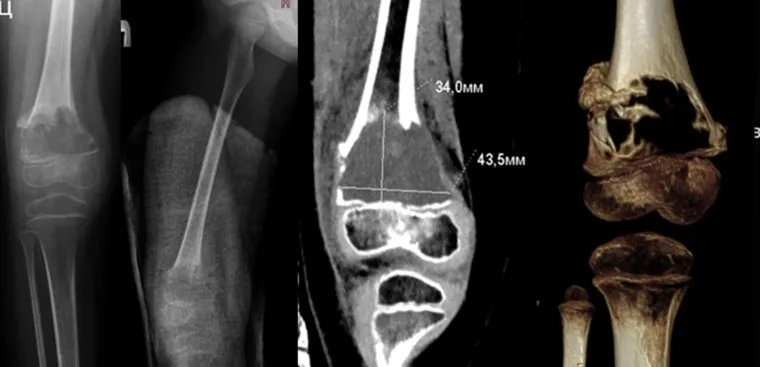

В Центре Илизарова в Кургане провели уникальную операцию 4-летней пациентке с редкой ортопедической патологией — аневризмальной костной кистой. Патология привела к перелому бедренной кости. Об этом URA.RU сообщили в пресс-службе медучреждения.

«4-летняя пациентка отделения №6 Клиники нейроортопедии и системных заболеваний была госпитализирована в Центр Илизарова с аневризмальной костной кистой. Редкое заболевание способно привести к серьезным осложнениям. Заболевание поражает метафизарные отделы трубчатых костей и позвоночника. В данном случае киста расположилась в правой бедренной кости ребенка», — рассказали нам.

Аневризмальная костная киста у ребенка достигла размера почти со спичечный коробок и полностью разрушила фрагмент бедренной кости, что спровоцировало перелом. Заболевание опасно осложнениями, включая деформации и укорочения конечности, а также нарушениями роста костей.

До лечения